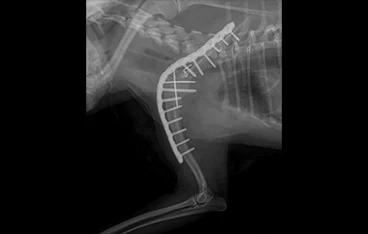

• PLATE

• PLATE 수술 전

PLATE 수술 후